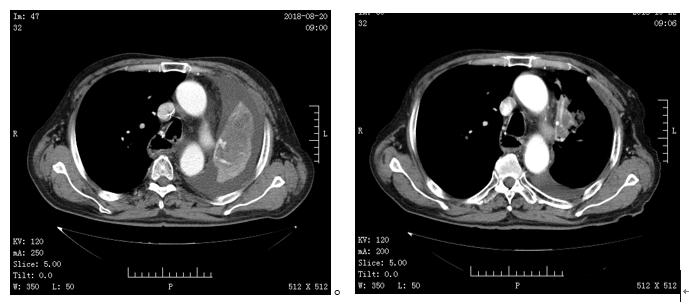

葛大爷家属治疗也特别积极,于是开始了与安罗替尼的同行路,刚开始服用一个周期时,葛大爷的症状减轻,且原来的肺不张情况开始有所缓解,以下是葛大爷服用两个月左右的复查CT,情况明好转,家里人和葛大爷特别激动,是安罗替尼使他们柳暗花明又一村,借用家属说的"确认过病情,孙主任是我对的人"。目前葛大爷仍在使用安罗替尼维持治疗,未发生乏力、高血压、出血、皮肤毒性反应 。

(左:2018.08.20 右:2018.10.22)且已经在服用第四疗程的援助药品,病情处于稳定,葛大爷的心情也慢慢好起来。2019-1-25号复查,病情稳定,葛大爷耐受良好目前一直在服用安罗替尼,疗效评价如下图所示: